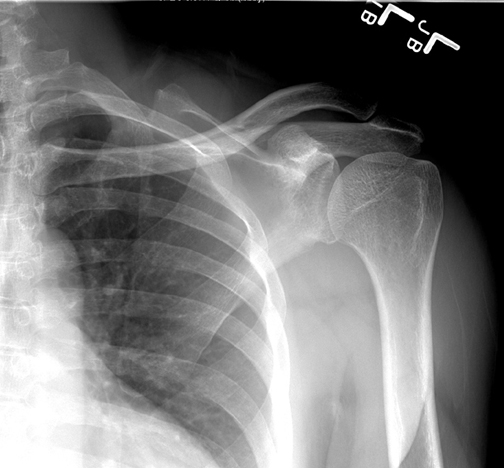

Identify the various parts seen. Click the image for labeling.